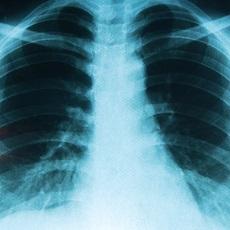

Lung cancer is cancer that forms in tissues of the lung, usually in the cells that line the air passages. It is the leading cause of cancer death in both men and women.

There are two main types: small cell lung cancer and non-small cell lung cancer. These two types grow differently and are treated differently. Non-small cell lung cancer is the more common type.

Lung cancer may not cause any signs or symptoms until the cancer is advanced. Sometimes the cancer is found during a chest x-ray done for another condition.

- May order certain imaging tests, such as a chest x-ray or chest CT scan